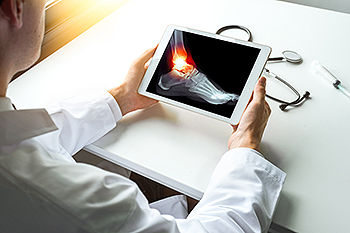

To figure out the cause of foot pain, podiatrists utilize several different methods. This can range from simple visual inspections and sensation tests to X-rays and MRI scans. Prior medical history, family medical history, and any recent physical traumatic events will all be taken into consideration for a proper diagnosis.

Achilles tendon injuries are diagnosed by a thorough physical evaluation, which can include an MRI. Treatment involves rest, physical therapy, and in some cases, surgery. However, various preventative measures can be taken to avoid these injuries, such as: